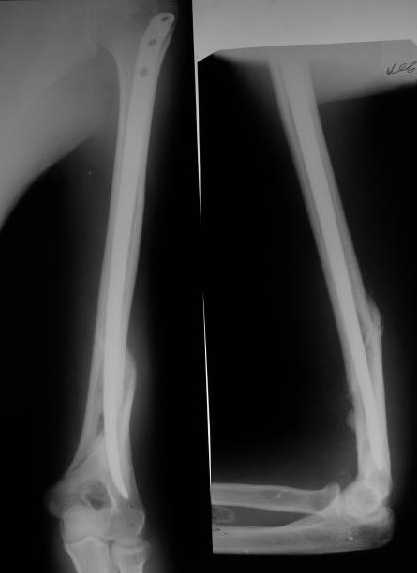

>антероградный - 30 процентов имеют боль в плече, связанную с повреждением ротаторной манжеты

Мы в последние годы все еще используем для переломов такой локализации эластичные титановые стержни (по мотивам ярославских разработок, Зверева-Ключевского). Такой стержень можно вводить не через сухожилие надостной мышцы, а дистальнее.

Снимки до, через 1 и 2 мес. после синтеза.